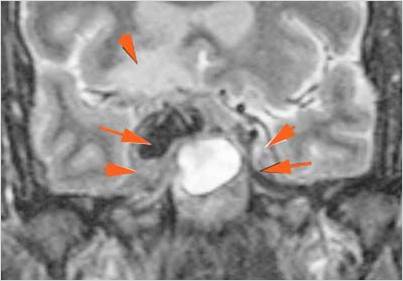

Intracranial

There is a subperiosteal fluid collection or abscess along the boney walls of the anterior or middle cranial fossa.

There is an epidural fluid collection or abscess along the boney walls of the anterior or middle cranial fossa.

There is a subdural fluid collection or abscess along the boney walls of the anterior or middle cranial fossa.

There is a subdural fluid collection or abscess along the falx cerebri or within the tentorium.

There is evidence of thrombus, thrombophlebitis or other occlusive or inflammatory process of the cavernous sinus.

There is evidence of inflammation of the distal internal carotid artery.

There is evidence of an infectious aneurysm.

There is brain edema specifically involving the frontal and temporal lobes.

There is cerebritis specifically involving the frontal and temporal lobes.

There is brain abscess specifically involving the frontal and temporal lobes.

There is likely meningitis, meningoencephalitis with complicating hydrocephalus or brain herniation.